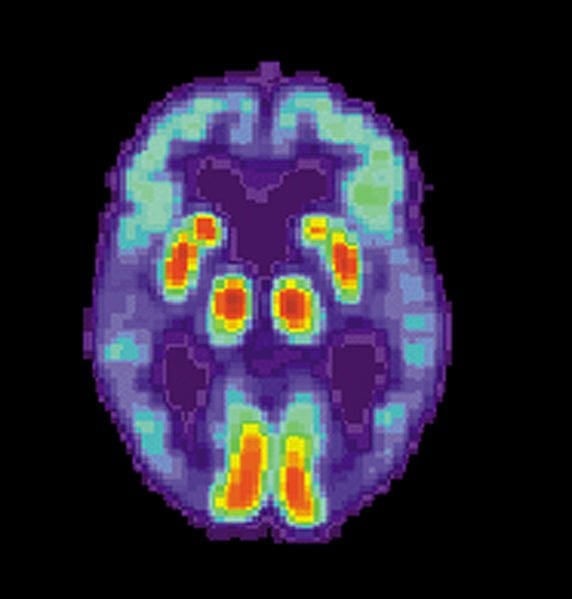

Image Source: The Alzheimer’s brain scan image is credited to the NIA/NIH and is in the public domain.